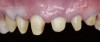

Fig 1. Preoperative extraoral view of a patient’s smile exhibiting compromised esthetic situation.

Figure 1

A 40-year-old patient presented with the chief complaint: “My teeth are cracking, and I would like to have my original bite.” Dental findings included Class I occlusion with slight misalignment between teeth Nos. 8 and 9. Generalized severe occlusal wear and slight Class I mobility of teeth Nos. 23 to 26 were noted. Caries lesions were found on teeth Nos. 2, 4, 6, 8, 9, and 14 and abfraction lesions on teeth Nos. 4, 5, 10, 11, 13, 20, and 21. Figure 1 through Figure 3 depict the preoperative situation. Full-mouth rehabilitation was suggested. The goals for the restorative treatment were management of erosive etiology, conservation of tooth structure, and long-term protection of the restorations. A diagnostic wax-up was instrumental in determining functional and esthetic treatment goals and establishing new anterior guidance (Figure 4). A comprehensive, step-by-step treatment approach was applied, which, after periodontal pretreatment, caries control, and provisionalization, included definitive preparation (Figure 5) and restoration of the maxillary anterior teeth to establish anterior occlusal guidance. CAD/CAM–fabricated full-contour monolithic high-translucent zirconia crowns (Katana™ UTML Ultra Translucent Multi-Layered, Kuraray Noritake Dental, kuraraynoritake.com) were fabricated (Figure 6 and Figure 7) and cemented with self-adhesive resin cement (Panavia SA, Kuraray Noritake Dental). Figure 8 demonstrates the cemented anterior crowns and refined conservative preparations of posterior teeth, which were performed with minimal tooth-structure removal. High-translucent monolithic zirconia onlays and crowns were fabricated (Katana Zirconia UT, Kuraray Noritake Dental) (Figure 9 to Figure 12). The posterior restorations were adhesively bonded following the APC zirconia-bonding concept. APC-Step A involved air-particle abrasion with 50-μm aluminum oxide at 1.5 bar with a chairside microetcher (Figure 13), followed by application (APC-Step P, Figure 14) of a special ceramic primer (ClearfilTM Ceramic Primer, Kuraray Noritake) with adhesive phosophate monomers (MDP). Relative moisture and contamination control was achieved with cotton rolls and retraction cords. Rubber dam placement, which is always preferred, was difficult in this situation. The enamel surfaces of the abutment teeth were selectively etched (Figure 15) with 35% phosphoric acid (K-Etchant Gel, Kuraray Noritake Dental) and the dentin conditioned (Figure 16) with a self-etch dentin primer (Panavia V5 Tooth Primer, Kuraray Noritake Dental). A dual-cure adhesive resin (Panavia V5 Paste Universal, Kuraray Noritake Dental) was dispensed directly into the restorations with an automix syringe. The restorations were inserted, and excess cement was carefully removed (Figure 17 and Figure 18) before light polymerization (Figure 19). Postoperative views depict the treatment outcome (Figure 20 to Figure 22).